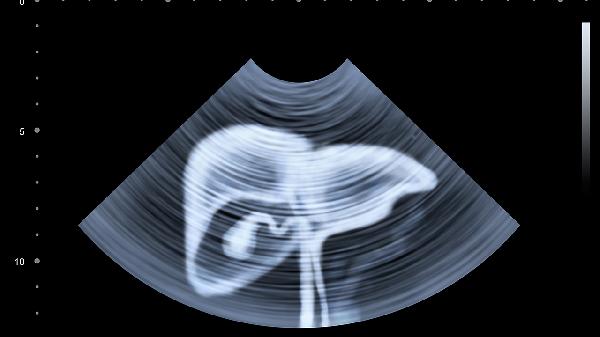

3、肝癌风险需长期监测。丙肝患者治愈后仍存在肝癌风险,尤其是肝硬化患者。定期进行肝脏超声和甲胎蛋白检测,可早期发现肝癌,提高治愈率。